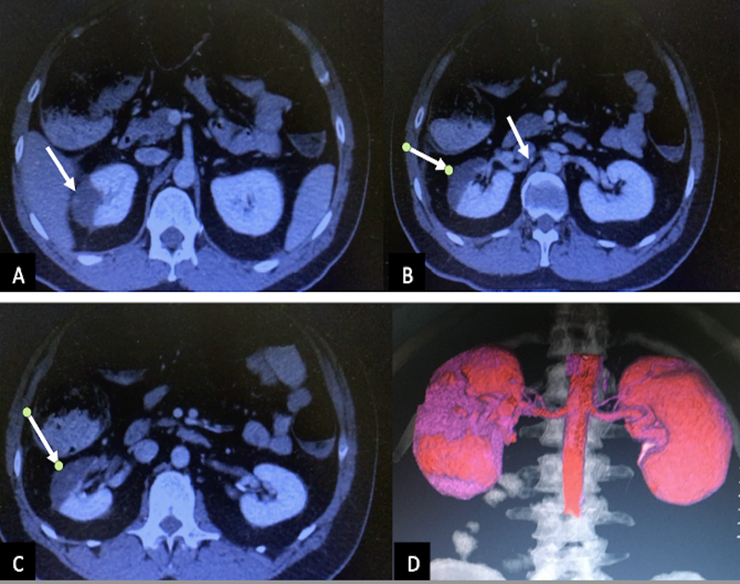

On 08/19, the patient reported abdominal distension with decreased bowel sounds, diffusely painful on deep palpation, not peritoneal. Oral tolerance is suspended, and a nasogastric tube is placed without gagging or vomiting. An abdomen-pelvis CT scan is requested, informing the proximal/middle third of the right renal artery, with images of lack of filling in its interior, and hypodense areas in the right kidney, of triangular morphology with a peripheral base, that are visualized during the contrasted phase consistent with renal infarcts (Fig. 2-3).

The axial abdominopelvic computed tomography image (A, B and C) revealed perfusion defects (arrows), which sharply demarcated a low attenuation lesion in the right kidney. There is visible thromboembolism in the renal artery (B, arrow). The coronal image (D) showed the areas without perfusion (violet color)

Figure 3: Axial abdominopelvic computed tomography image